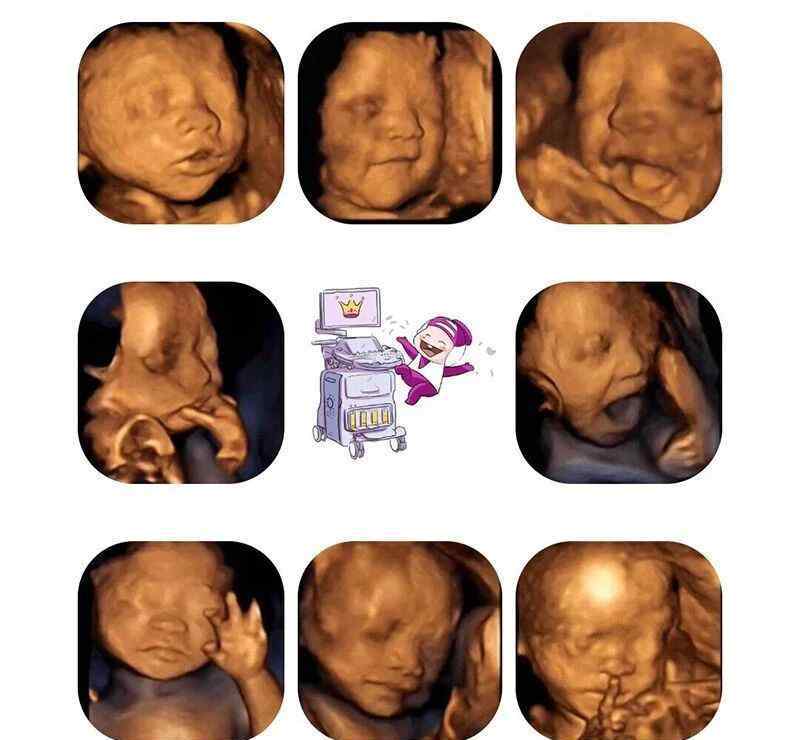

三维彩超是照片,是静态数据的;超声波影象(四维彩超)是影象,是动态性的,能够让宝妈妈见到胎宝宝一连串的姿势。

三维彩超只有是某一时间点上的相片;超声波影象(四维彩超)选用四维显像技术性,查验結果更加形象化,立体式,并对总体目标目标开展持续多维扫描仪,能够刻录成光碟。

超声波影象(四维彩超)已不是只是觉得小宝宝的吸气和健身运动,只是能够亲眼看到她们的一举一动和聪明的秀容。让爸爸宝妈妈提早跟胎儿“碰面”,见到胎宝宝在孕妈内的实时动态,如笑容、打哈欠、皱眉、扮鬼脸、吸手指头、懒腰、伸舌头等。